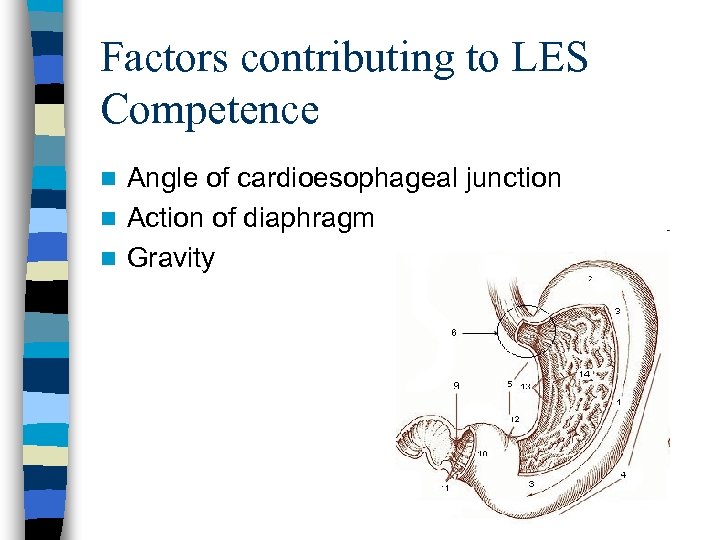

Factors contributing to LES Competence Angle of cardioesophageal junction n Action of diaphragm n Gravity n